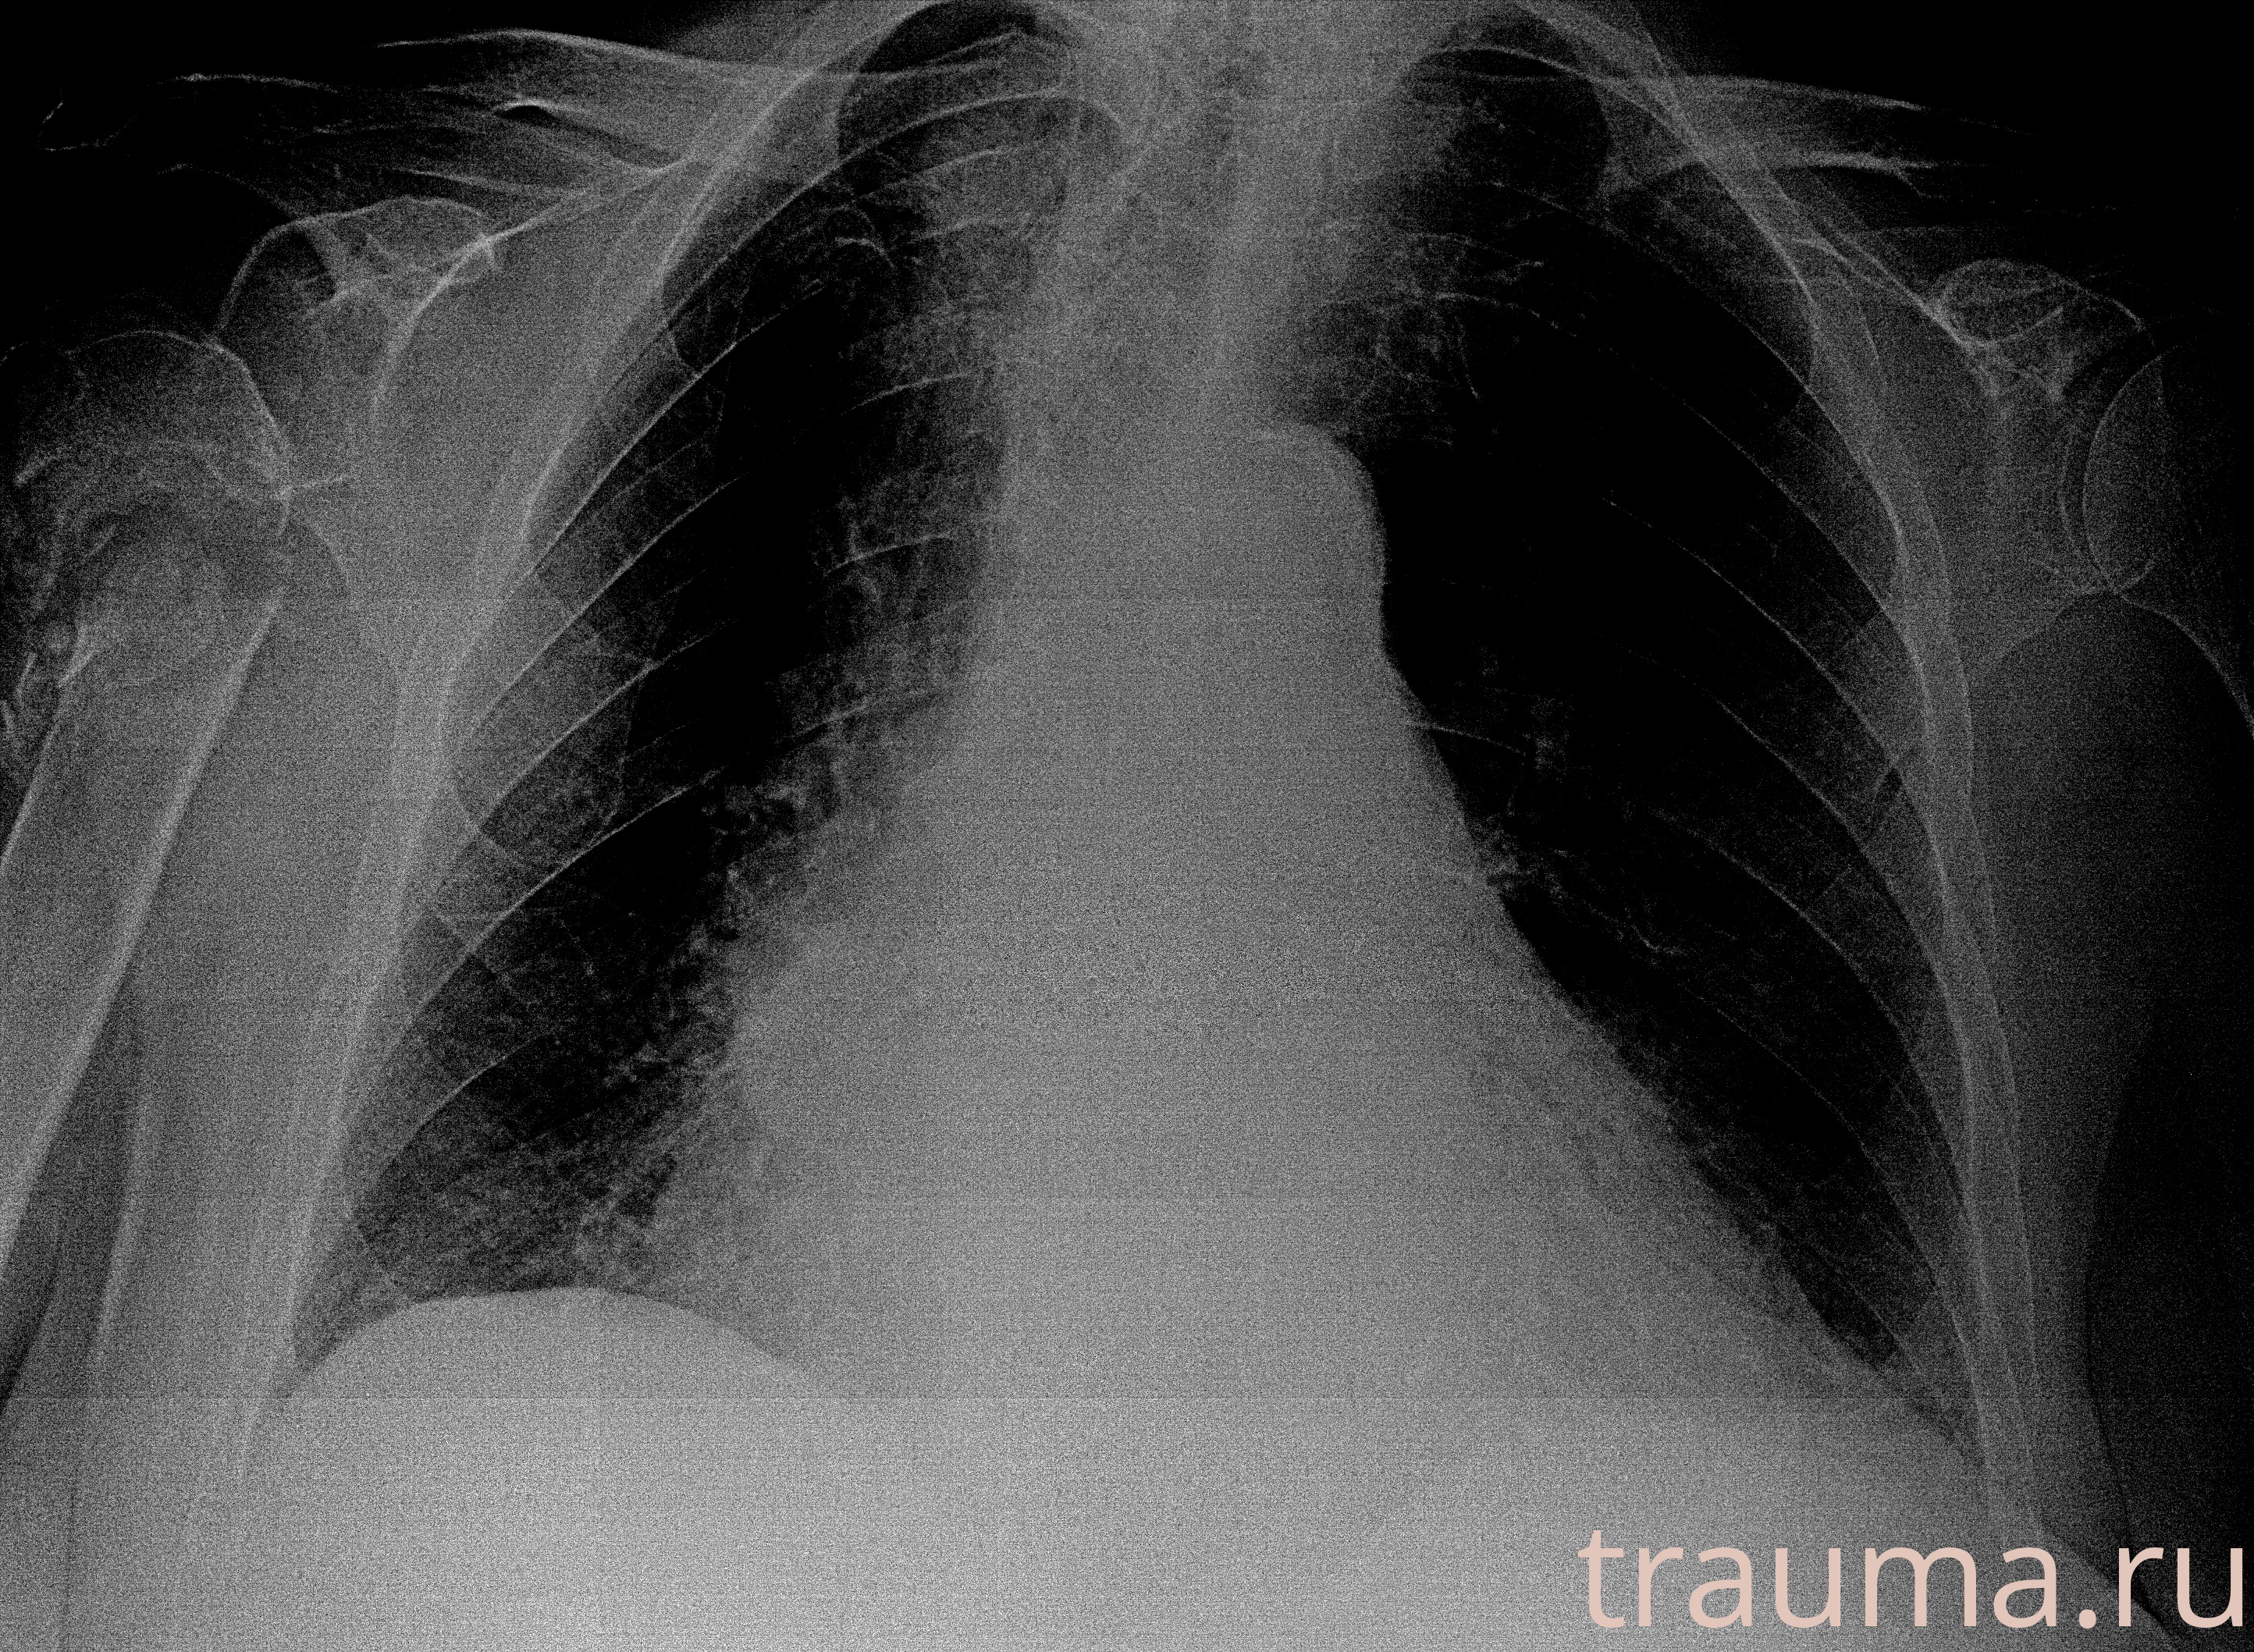

Рентгенограммы

Рентген на дому: по вашему адресу приезжает врач-рентгенолог, травматолог-ортопед с мобильным рентгеновским аппаратом, проводит диагностику травмы или заболевания, делает необходимые рентгенограммы, дает рекомендации по дальнейшему лечению. Получить качественные снимки в домашних условиях возможно благодаря уникальной методике, разработанной МосРентген Центром для института  Склифосовского